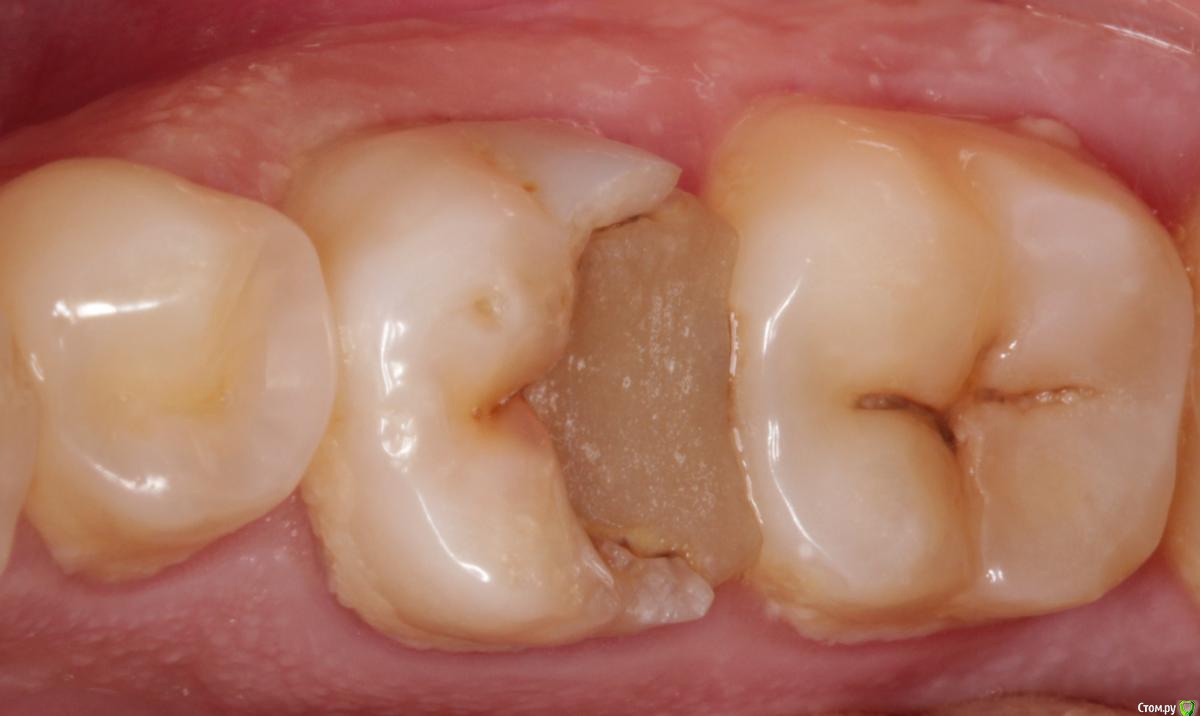

Витторио Орлионе Опубликовано 30 марта, 2017 Поделиться Опубликовано 30 марта, 2017 (изменено) Обратился пациент 1988 года рождения с жалобами на постоянные ноющие боли, усивиающиеся при накусывании на зуб беспокоящие его на протяжении 2х дней. Объективно зуб 3.7 ИНТАКТНЫЙ! ни пломб, ни кариеса не обнаружено, перкуссия его болезненная, температурная проба отрицательная, при накусывании на валик реагировал именно этот зуб. Поскольку зуб 3.6 стоял со старой пломбой и навиающими краями было решено пройтись ультразвуком, поскрести по сусекам слегка заполировать пломбу и оставить метрогил. На следующий день поднялась температура.Через день пришёл на приём. Зуб 3.7 сильно реагирует даже на слабое прикосновение.Не решился депульпировать, так как не вижу объективных причин для такого развития, откуда вообще периодонтит в интактном зубе?!? Пациент отправлен домой, так сказать под наблюдение.Верхние зубы также интактны, все антагонисты в наличии.Как быть и что делать? Изменено 30 марта, 2017 пользователем Витторио Орлионе 1 1 Ссылка на комментарий

DmitrySH Опубликовано 30 марта, 2017 Поделиться Опубликовано 30 марта, 2017 Объективно зуб 3.7 ИНТАКТНЫЙ! ни пломб, ни кариеса не обнаружено, перкуссия его болезненная, температурная проба отрицательная, при накусывании на валик реагировал именно этот зуб. А если внимательно посмотреть снимок, то на корне 37 нормальная такая кариозная полость Ссылка на комментарий

DmitrySH Опубликовано 31 марта, 2017 Поделиться Опубликовано 31 марта, 2017 (изменено) Полость не вижу На границе эмали и цемента корня нет кариеса? http://s010.radikal.ru/i311/1703/b9/fc60e3737466.jpg Изменено 31 марта, 2017 пользователем DmitrySH Ссылка на комментарий

Л Ю С Я Опубликовано 1 апреля, 2017 Поделиться Опубликовано 1 апреля, 2017 На границе эмали и цемента корня нет кариеса?Думаю это артефакт. Нужен визуальны осмотр, даже если и есть, то явно не до пульпы 1 Ссылка на комментарий

Жандос Муратович Опубликовано 1 апреля, 2017 Поделиться Опубликовано 1 апреля, 2017 На границе эмали и цемента корня нет кариеса? кариес есть однозначно,депульпируйте 7,зачем мучаете пациента. Ссылка на комментарий